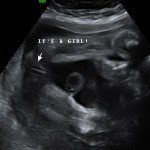

Baby Boutique and gender reveal party supplier.

Our baby boutique offers many unique items to announce the gender of your little one. We offer confetti cannons, powder cannons, flutterfetti sticks, and smoke bombs. We also have a variety of infant outfits and blankets. Our boutique features ultrasound photo frames and unique frames and gifts for grandparents. Record your baby’s heartbeat in one of our adorable animals for a keepsake you will cherish forever.